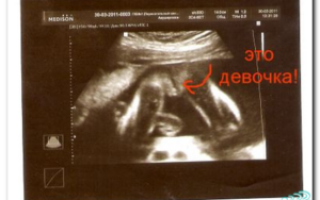

Часто беременные сталкиваются с тем, что УЗИ указывает на девочку, а на свет появляется мальчик, или наоборот.

В первую очередь, связано это со сроком беременности — вероятно, он еще мал для того, чтобы достоверно определить пол будущего ребенка. Первое плановое УЗИ приходится на период 11-13 недель.

Размеры плода еще настолько малы, что врач УЗИ диагностики может ошибочно предположить тот или иной пол. Поэтому не следует полностью полагаться на эти результаты. В некоторых случаях предположение подтверждается в дальнейшем, однако следует расценивать это как простое совпадение.